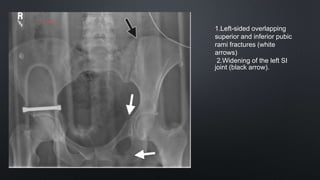

1.Left-sided overlapping

superior and inferior pubic

rami fractures (white

arrows)

2.Widening of the left SI

joint (black arrow).